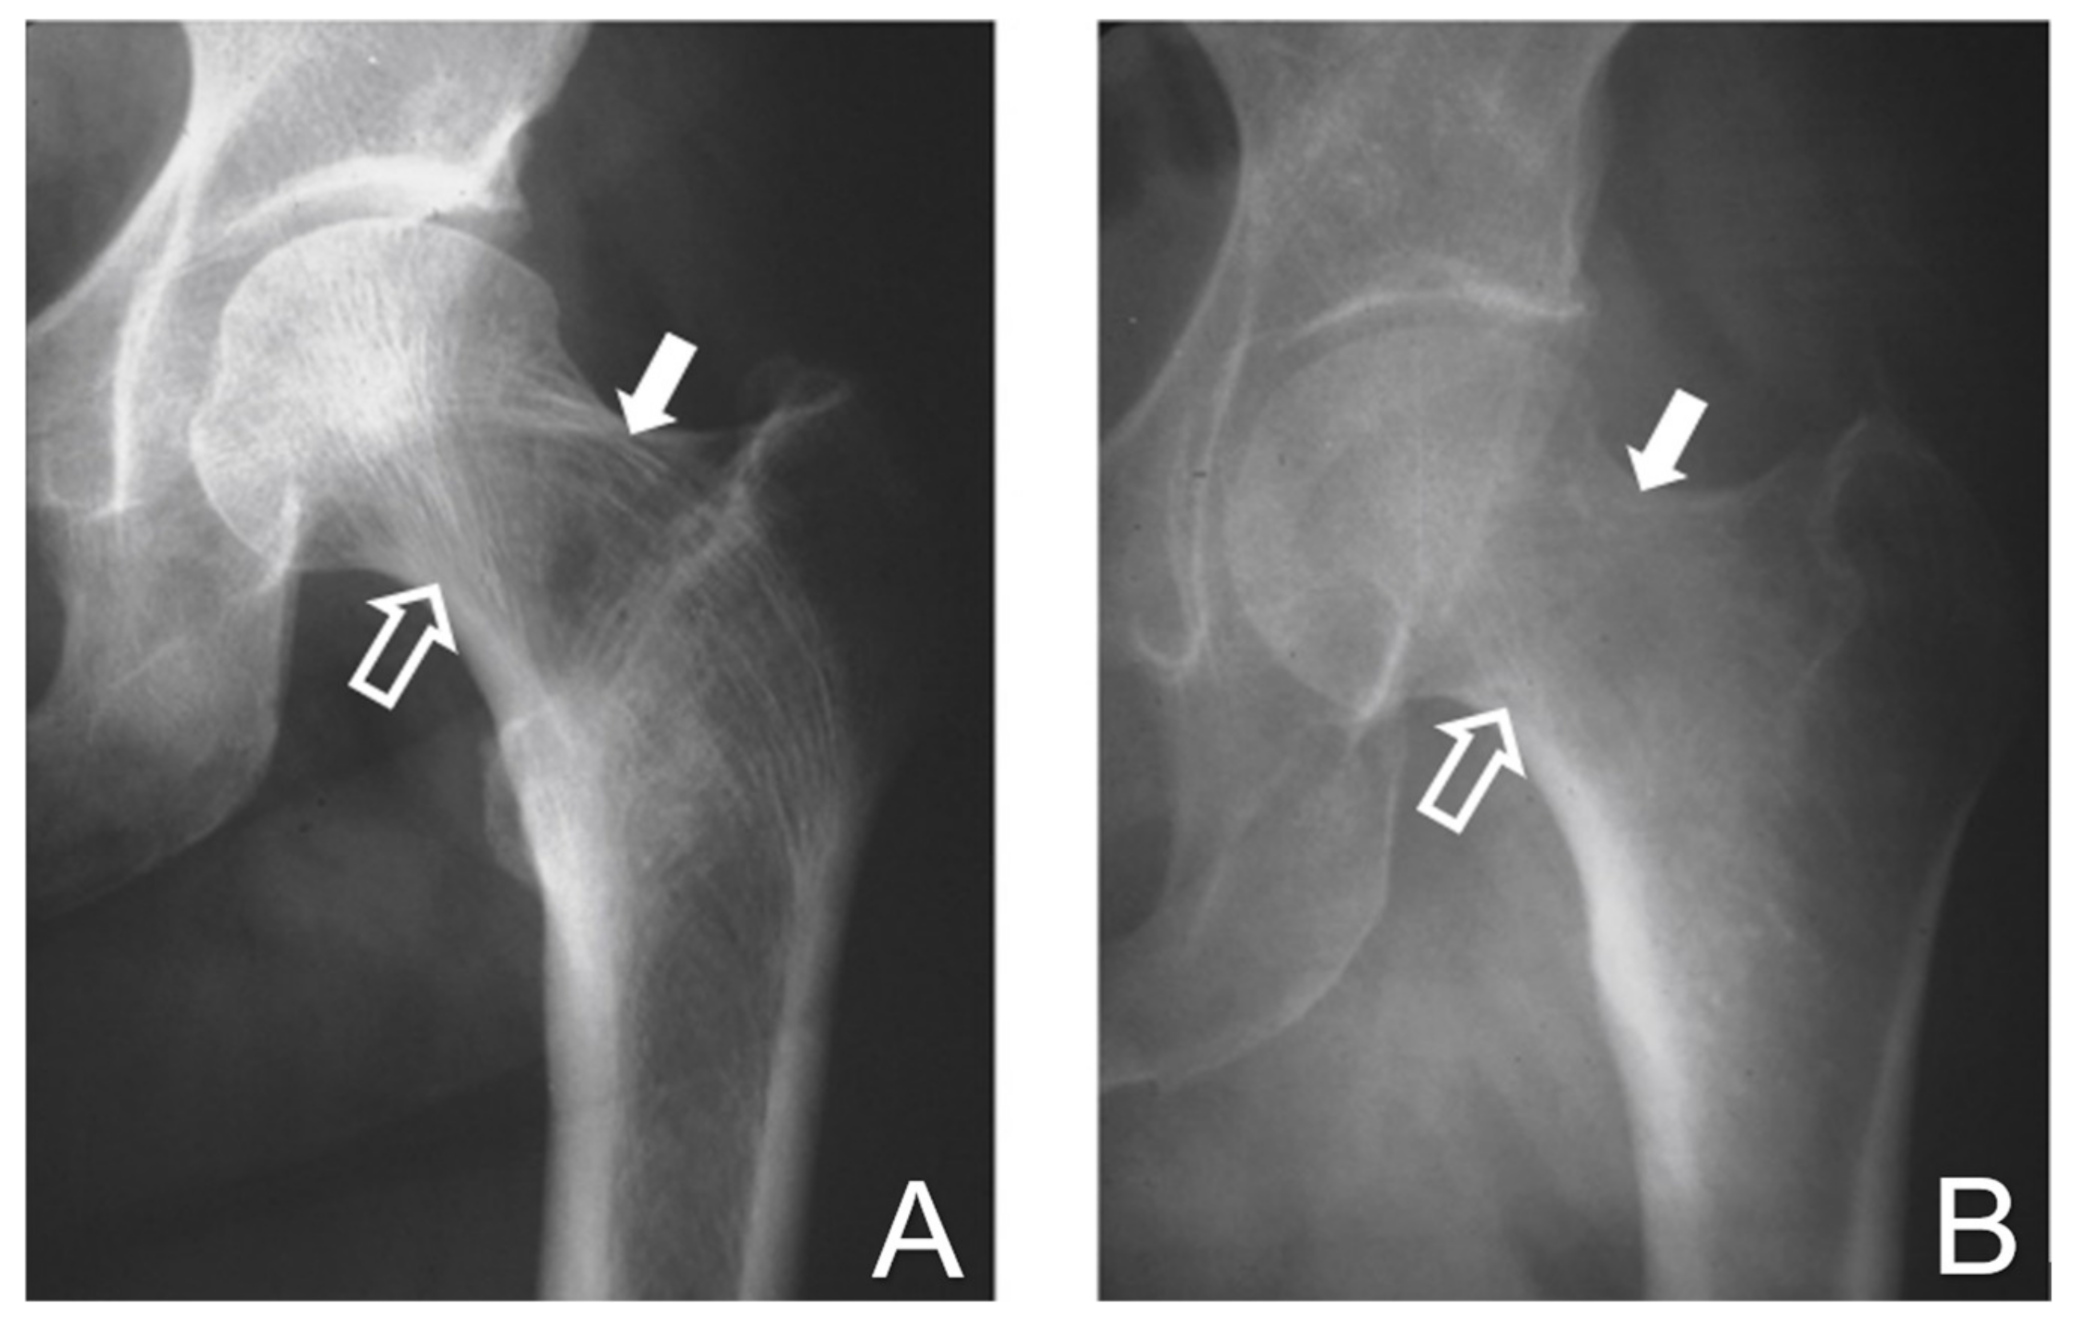

2.1. The Demineralized Bone Matrix-Induced Endochondral Bone Formation Model

2.2. Enhancement of Cell Differentiation in the DBM-EO Model by PEMFs